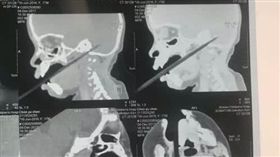

因為車禍住院 一 照X光卻讓她傻眼

近期,中國河南一名29歲女子,因為發生車禍而緊急住院...

童邊吃邊玩跌倒!筷子刺穿腦袋超驚悚

中國大陸一名1歲半女嬰晨晨(化名),用餐時間邊吃邊玩...

爸媽吵架波及男嬰 長長鋼管直插腦門

中國河北省石家莊市20日發生一起恐怖的家庭意外,一對...